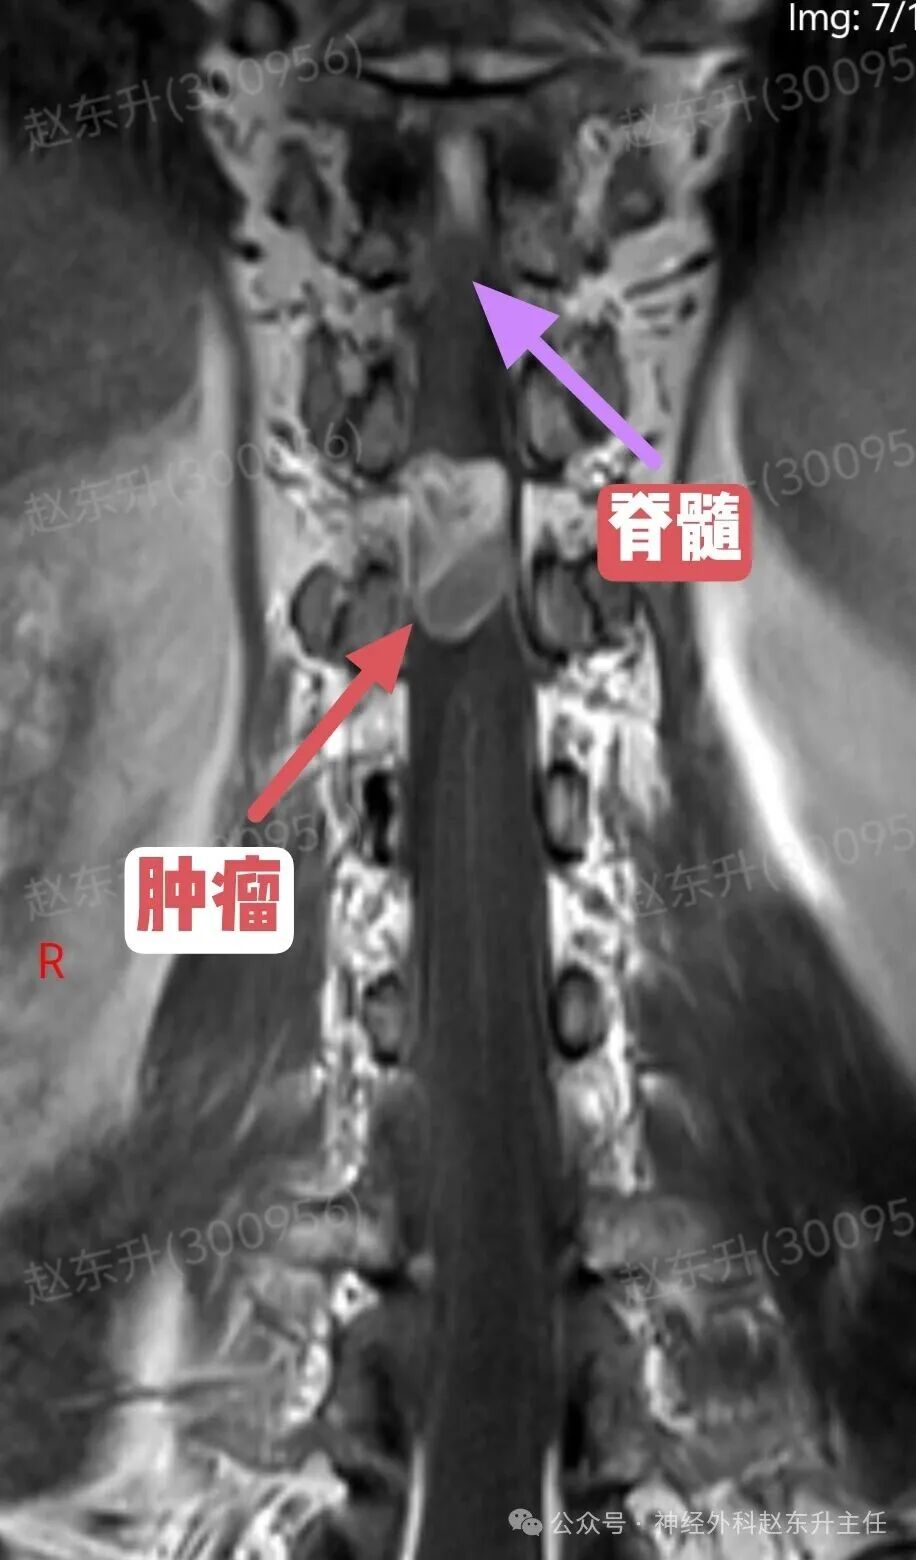

今天介绍一位58岁的男性患者,因为腰背部疼痛半年入院的。他半年前出现腰背部疼痛疼痛评分4-5分半双下肢乏力,但可独立行走。症状尚可忍受,但随后症状逐渐加重,疼痛有7-8分,吃药打针康复理疗。效果不明显,随后到医院查了一个磁共振,发现胸11-12水平椎管内巨大的肿瘤,肿瘤长在脊髓腹侧,外院的医生看了之后认为手术风险太大,不敢做,随后他来到西安市红会医院神经外科找到赵主任。入院后完善术前检查。随后在全麻下进行了肿瘤全切术中使用显微镜并进行术中电生理监测尽最大可能的保护脊髓神经,最终肿瘤予以全切,术后神经没有损伤,下肢可以正常下地活动大小便也正常,患者顺利出院了。

症状早期症状不典型:可能仅表现为相应神经根支配区的疼痛或感觉异常脊髓压迫症状:随着肿瘤增大,从前方直接压迫脊髓,可导致:运动功能障碍为主:由于压迫脊髓前角和皮质脊髓束(运动传导通路),常早期出现肢体无力、僵硬、肌肉萎缩,且可能比感觉障碍更早、更明显。感觉障碍:表现为受压平面以下的痛温觉减退(因压迫脊髓丘脑束)。括约肌功能障碍:大小便困难,出现较晚。不对称症状:由于肿瘤偏于一侧,症状常从一侧开始。影像诊断(MRI是金标准)位置:明确显示肿瘤位于椎管内、脊髓的正前方或前外侧形态与信号:常呈“哑铃形”,部分肿瘤通过椎间孔向椎管外生长。T1加权像呈等或稍低信号,T2加权像呈高信号,增强后显著不均匀强化关键观察点:放射科和外科医生会重点关注肿瘤与脊髓前动脉、椎动脉(颈段)的关系,以及脊髓受压移位的程度。